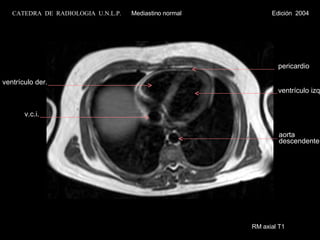

RM axial T1 pericardio ventrículo izq. ventrículo der. v.c.i. aorta descendente CATEDRA  DE  RADIOLOGIA  U.N.L.P.   Mediastino normal  Edición  2004

RM axial T1pericardio ventrículo der. ventrículo izq. septo Interventric. v. ácigos aorta descendente CATEDRA DE RADIOLOGIA U.N.L.P. Mediastino normal Edición 2004